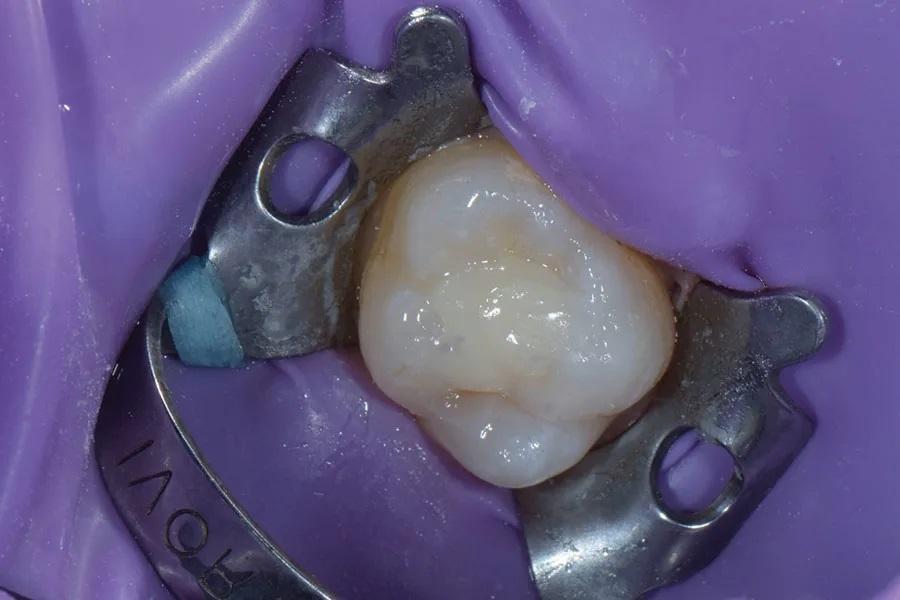

Следует отметить: внедрение стержня микрокисти в окклюзионный «штамп» помогает затем правильно ориентировать его на финальном слое композита при перенесении дооперационной окклюзионной анатомии. Для ориентации также можно пометить отвержденный «штамп» черной точкой по щечному или язычному краю. После отверждения «штамп» снимают с зуба (Фото 4).

Фото 4. Светоотвержденный окклюзионный «штамп» с прикрепленной к нему микроручкой сняли с поверхности зуба 2.6.